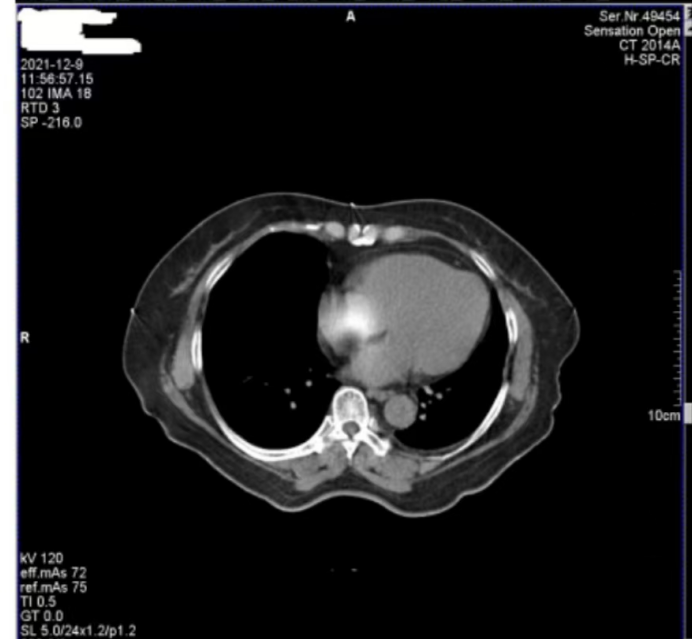

醫(yī)院反映,西門子Definition型CT機(jī)在進(jìn)行患者掃描時(shí),圖像上會(huì)偶發(fā)兩種偽影。一種是斜線狀偽影(圖 1),另一種是中心不規(guī)則高密度偽影(圖 2)。其中,斜線狀偽影對(duì)診斷影響較大,時(shí)常導(dǎo)致醫(yī)生無法準(zhǔn)確判斷患者病灶情況,醫(yī)院希望我們盡快排查并解決問題。

圖2

接著,我們將目光轉(zhuǎn)向圖 2 中的中心不規(guī)則高密度偽影。為了找出偽影成因,我們對(duì)設(shè)備的多個(gè)關(guān)鍵部件進(jìn)行了檢查。首先查看了玻璃條、探測(cè)器表面以及準(zhǔn)直器表面,確認(rèn)這些部位是否沾有造影劑,因?yàn)樵煊皠埩粲袝r(shí)會(huì)導(dǎo)致偽影產(chǎn)生,但檢查結(jié)果顯示這些部位均干凈無污。

隨后,我們檢查了特氟龍濾線器部件。特氟龍部件采用金屬材質(zhì),具有較高的穩(wěn)定性,通常不會(huì)出現(xiàn)斷裂等情況,因此可以排除因特氟龍部件異常導(dǎo)致偽影的可能。考慮到這種中心偽影是偶發(fā)出現(xiàn)的,我們開始推測(cè)其他可能性。結(jié)合球管的結(jié)構(gòu)和工作原理,我們懷疑是球管內(nèi)部存在雜物。球管內(nèi)部有油路循環(huán)系統(tǒng),若有雜物混入其中,在曝光過程中,當(dāng)雜物恰好處于出射線的位置時(shí),就會(huì)對(duì)射線產(chǎn)生干擾,從而在圖像中心形成不規(guī)則的高密度偽影。

綜合以上分析,圖 1 中的斜線狀偽影由球管打火引起,且已嚴(yán)重影響診斷;圖 2 中的中心偽影雖成因未完全確定,但推測(cè)與球管內(nèi)部雜物有關(guān)。鑒于球管打火問題的嚴(yán)重性以及兩種偽影可能存在的關(guān)聯(lián)性,我們判斷需要更換球管來徹底解決問題。

此次維修案例中,更換球管后兩種偽影均消失的結(jié)果,不僅證實(shí)了圖 1 中斜線狀偽影由球管打火導(dǎo)致的判斷,也驗(yàn)證了我們對(duì)圖 2 中心偽影成因的推測(cè)是正確的,即球管內(nèi)部雜物在油路循環(huán)過程中,于曝光時(shí)處于出射線位置而造成了中心偽影。